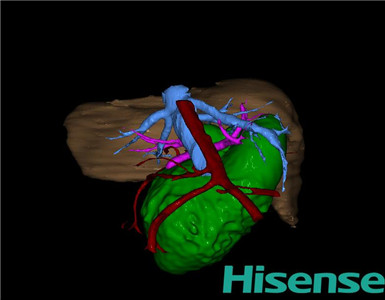

术前三维重建:

重建图片

将0.625mm双源薄层CT资料的静脉期和动脉期Dicom格式文件导入海信CAS系统。

通过调节窗宽窗位调整CT序号,对肝实质,胆囊,胆总管,下腔静脉,肝动脉、门静脉及肝静脉等进行三维重建;系统自动计算肝脏体积。

术前手术方案的规划。